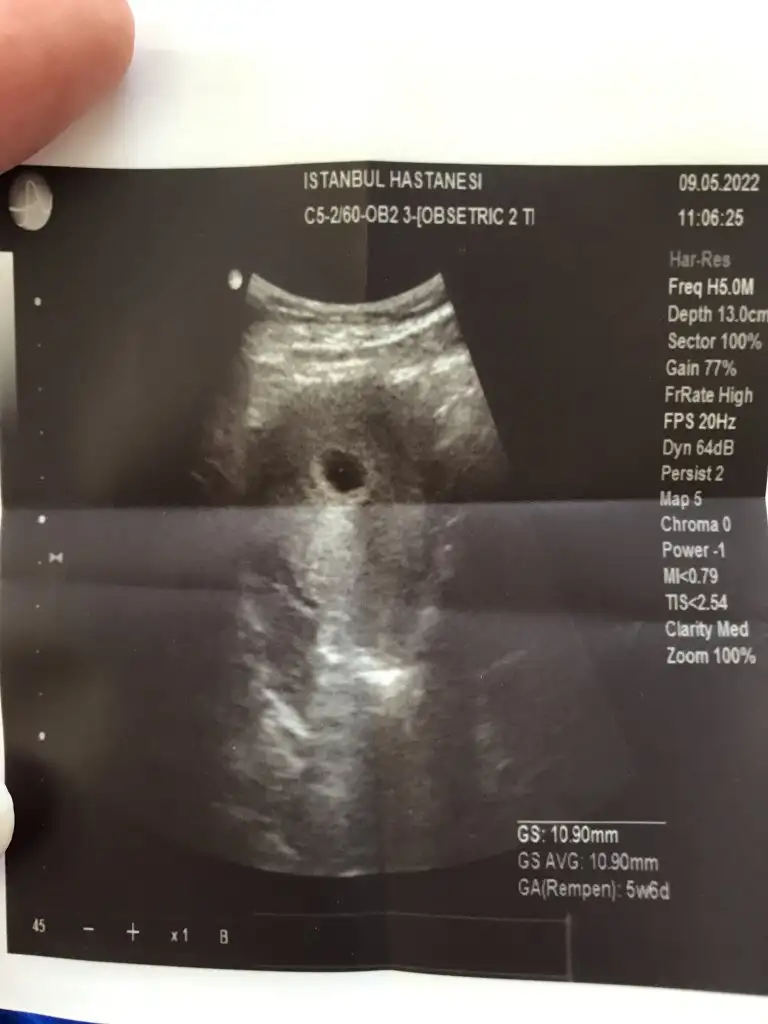

5+6 karından ultrason canım